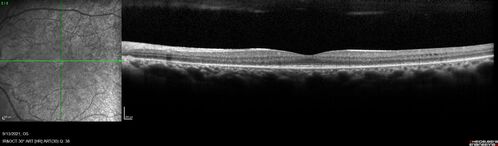

Ocular Lymphoma - Initially presented like auto-immune retinopathy

43 year old man: initial presentation - The vision in the left eye is blurry and opaque for about 2 weeks.  In the central of the vision, when he covers the right eye, in the center of the left eye there is a film with a light in the middle.  This has never happened before.  He has not been sick for the last few months.  A few weeks ago he saw waves on the floor when looking down but that has gone away.  Since the vision loss started the vision has not changed much.  The central vision is not getting better.

Labs normal.  One positive antiretinal antibody - Arrestin

VA improved over 2 months to normal.  Then the patient had 2 more episodes of self-limited vision loss (no treatment).  Then 2 years later he presented with a diagnosis of CNS lymphoma and later developed subretinal deposits (last images)